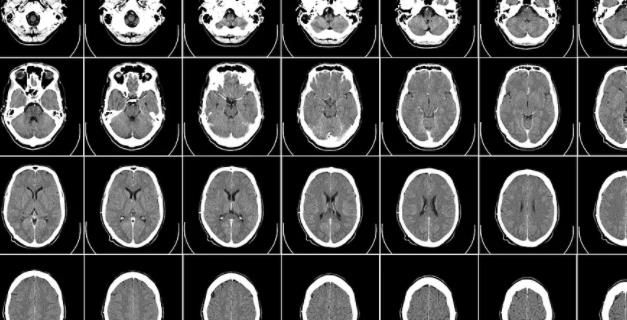

CT는 Computed Tomography의 약어로 X선을 사람의 몸에 투과해하여 흡수차이를 컴퓨터로 재구성하여 인체의 단면영상이나 3차원적인 입체 영상을 얻는 방법입니다.

CT의 경우 흉부CT,복부CT,3차원 혈관조영CT,심장관련 CT등 다양한 인체별 CT촬영으로 인체의 상태를 진단 할수 있습니다.

CT는 인체에 X선을 투과해 뼈와 단단한 조직 내부를 확인 하는데 용이 하며 대부분 장기를 CT로 확인 할수 있습니다.

복부질환,흉부,폐암,폐의 염증성 질환,만성기관지 질환등과 같은 폐질환을 CT로 진단이 가능합니다.